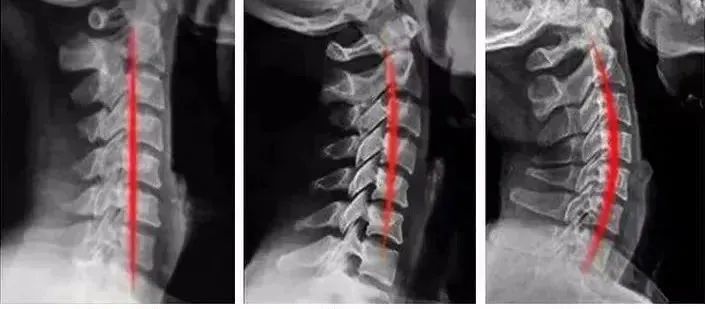

长时间睡这款安眠枕,对我们的颈椎也是非常友好的,可以帮助我们恢复健康的生理曲线!

用户@辰辰,使用了一段时间,从含羞驼背,变成了美丽的天鹅颈,气质直接提升了好几个档次!

小编同事坚持用下来,惊喜的发现,颈椎在慢慢恢复健康的生理曲线,可以说是真正的助眠又护颈的好枕头。